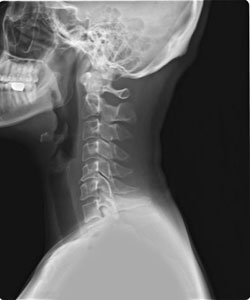

오늘 건강 정보는 목디스크 증상과 원인에 대해 알아보겠습니다. 엑스레이로 목을 촬영하면 목뼈가 c 곡선을 유지하는 것이 정상이라고 합니다. 하지만 요즘은 그렇지 않은 경우가 많은데요. 책상 앞에 앉아 있는 시간이 많기 때문에 머리를 숙이고 책을 보거나, 휴대 전화와 태블릿을 사용함으로써 잘못된 자세를 취하고 있기 때문에 목뼈의 배열이 흐트러지는 경우가 많습니다.

목을 받쳐주는 뼈를 경추라고 하는데 여기는 뼈가 7개 있고 이 뼈 마디마다 디스크라는것이 있습니다. 이 디스크의 역할은 척추 뼈 사이에 충격을 완화하고 운동할 수 있게합니다. 목디스크는 퇴행성 척추 질환으로 목 주위 근육, 인대가 장기간 압력을 받고 퇴행하여, 디스크가 자신의 역할을 하지 못하고 밀려나고 통증과 같은 목디스크 증상을 보이는 질병입니다. 이 디스크의 위치가 어디에 있는지에 따라 목 이외에도, 손이 저리거나 어깨가 아프고 두통과 같은 다른 목 디스크 증상을 일으킬 수 있습니다. 만약 여러분이 디스크를 그대로 방치하면, 몸이 마비되거나 호흡이 곤란한 상황에 처할 수 있기 때문에 여러분의 관심을 필요로 할 것입니다.